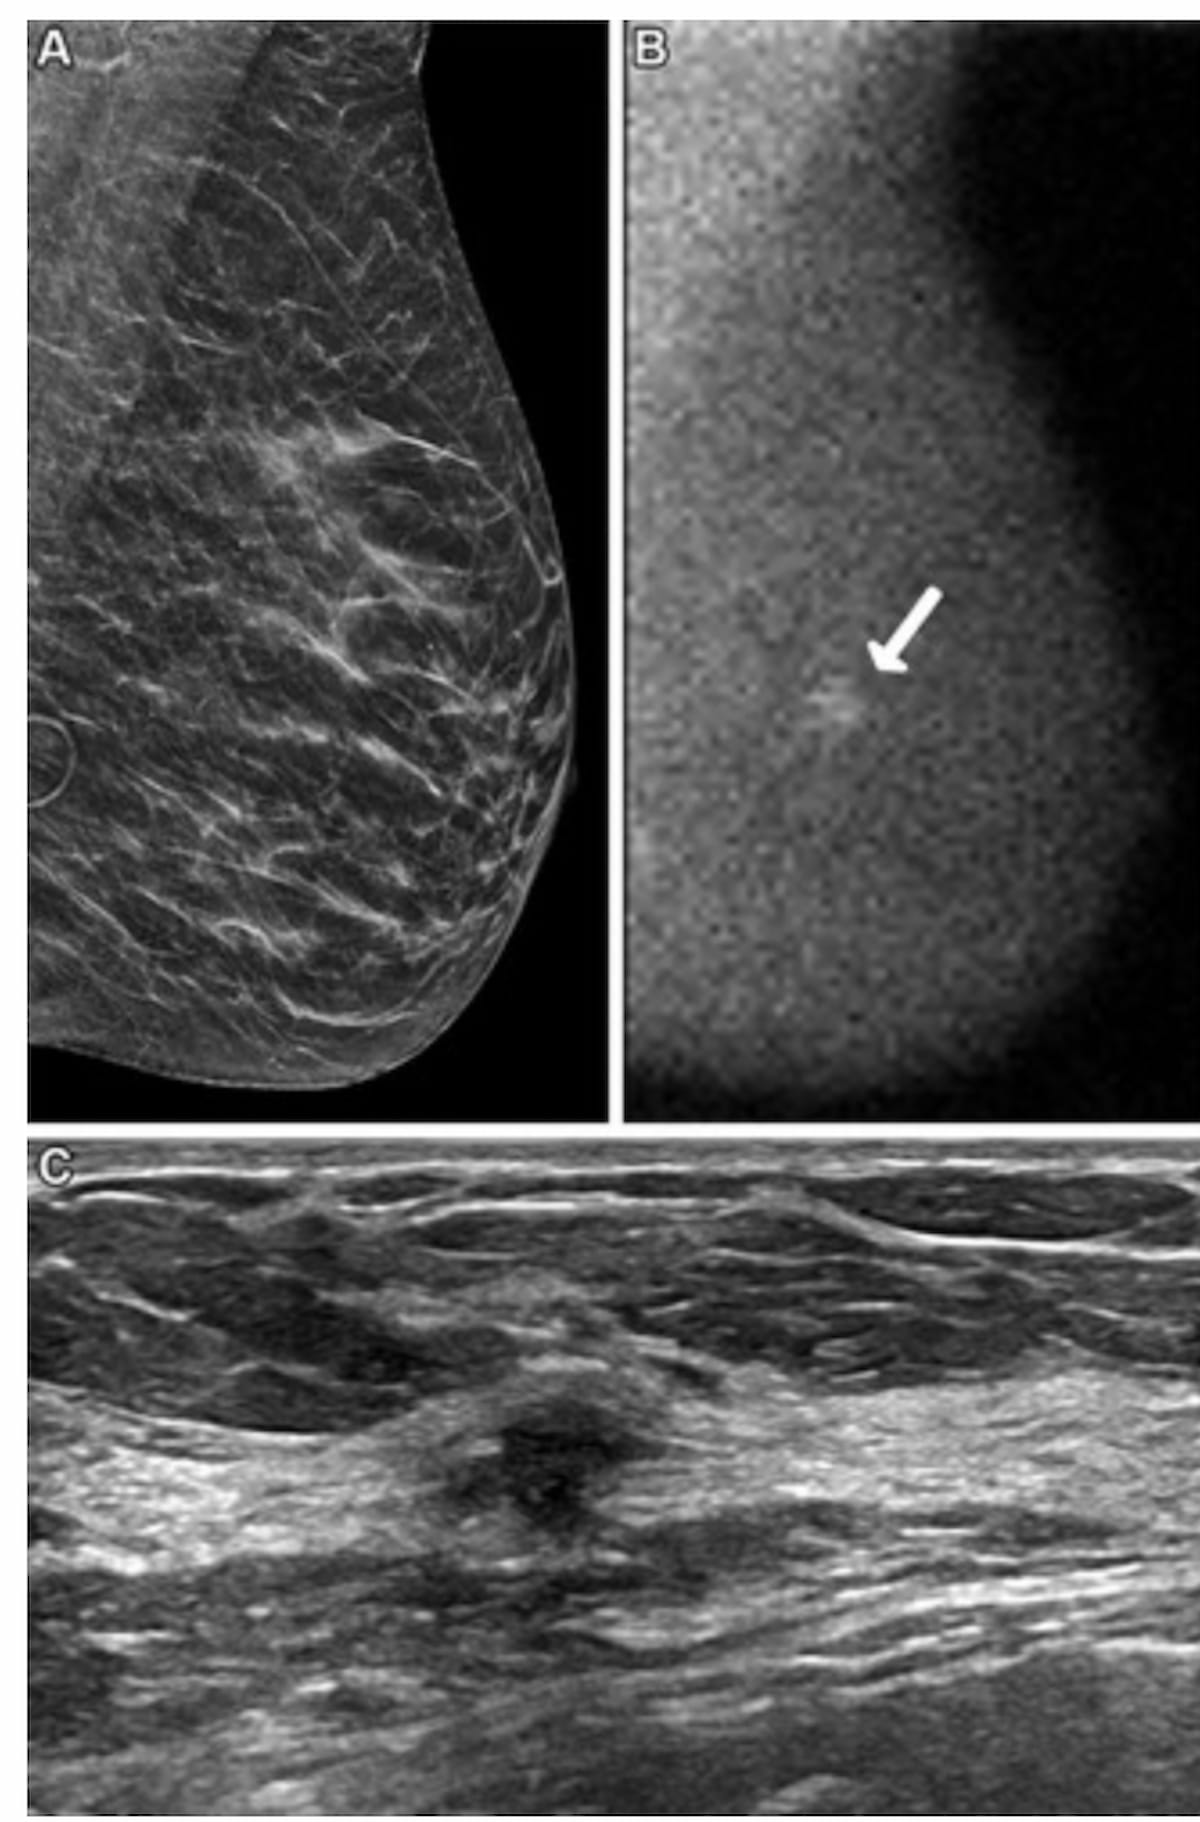

Here one can see a screening DBT image (A), molecular breast imaging (MBI) (B) and breast ultrasound (C) for a 62-year-old woman. While DBT was interpreted as negative, the MBI view revealed a 0.9-cm non-mass focal area of uptake at year one and ultrasound showed a suspicious mass 4 cm from the nipple. Subsequent biopsy results confirmed grade 2 invasive ductal carcinoma. (Images courtesy of Radiology.)